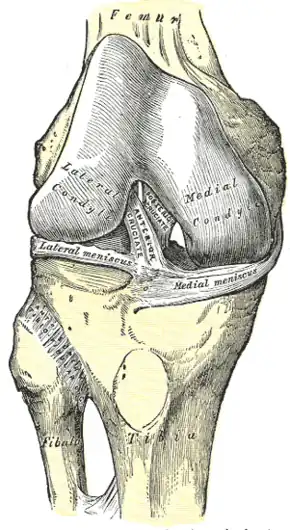

Right knee-joint, from the front, showing interior ligaments. | |

The superior tibiofibular articulation (also called proximal tibiofibular joint) is an arthrodial joint between the lateral condyle of tibia and the head of the fibula.

The contiguous surfaces of the bones present flat, oval facets covered with cartilage and connected together by an articular capsule and by anterior and posterior cruciate ligaments.